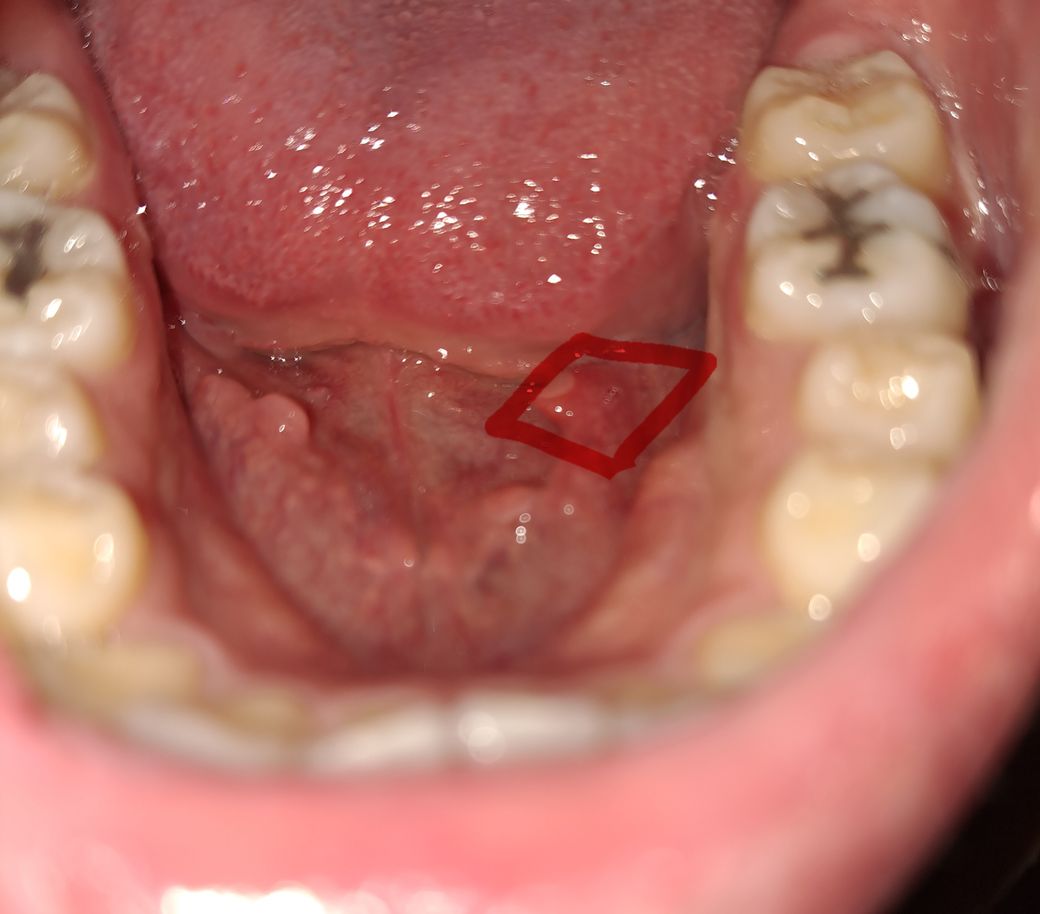

혀 아래 이물감이 드는 뭔가가 났어요.

오늘 갑자기 뭔가 혀에 만져져서 봤더니 저런게 생겼어요.. 조금 길쭉한 사각형 모양으로 살이 튀어나왔어요

아프지는 않는데 불편해서 뭔지 너무 궁금합니다.

사진으로 봐선 단순 섬유성 과증식일 수도 있으나 혀 밑 혈관(설하정동맥)과 관련된 질환일 수도 있을 것 같습니다. 구강내과가 진료과로 있는 치과 가서 한번 체크해보시기 바랍니다.

혀 아래에는 저렇게 주름이 잡혀 있는데요. 간혹 해당부위에 염증이 생기기도 합니다. 사진상으로 보기에는 염증이 있는 것으로 보이고 보통 시간이 지나면 괜찮아지니 너무 걱정하지 않으셔도 되겠습니다. 혹시 해당 병소의 크기가 커진다거나 통증이 심해질 경우에는 치과에 내원해보시는 것이 좋겠습니다.